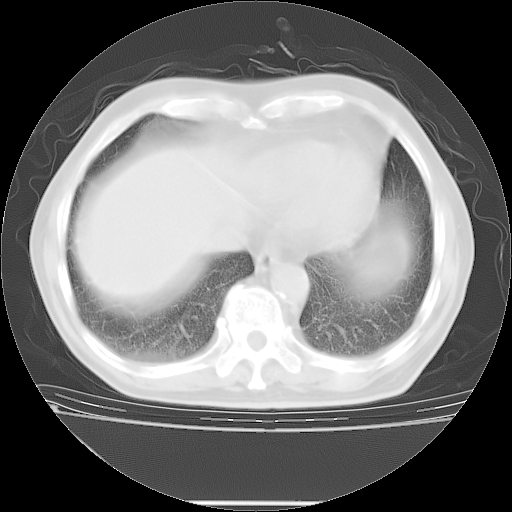

今天复查肺部CT,发现双肺广泛磨玻璃样改变。所以我把3月19日和5月9日相隔50天的肺部CT上传。请大家会诊。

5月9日肺部CT(在4月27日齐鲁医院肺部CT描述部分肺组织磨玻璃样改变,12天后肺组织广泛磨玻璃样改变)

大致读了系列胸部CT:纵隔窗无明显异常,肺窗:从4、27至今:主要是双肺中下野外带可见毛玻璃样改变,目前处于急性肺泡炎阶段,至于原因考虑1、结替组织或胶原血管性疾病所致?2、恶性疾病如恶组在肺部所致的表现或细支气管肺泡癌?3、药物或其它原因如肺蛋白沉着症所致肺泡炎目前不太可能?总之,明天就去请我院的呼吸科、感染科、血液科和临免专家会诊哈。